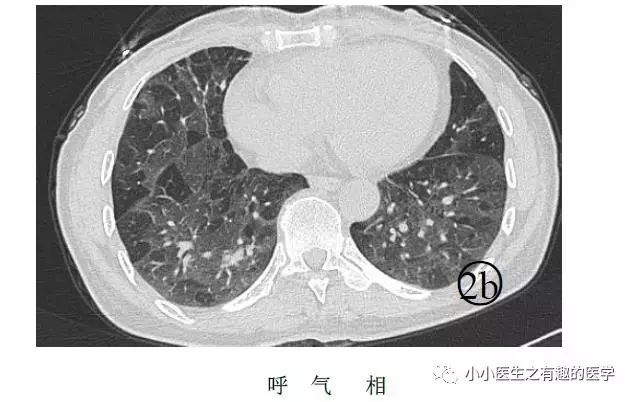

马赛克征象:由于气道疾病或肺血管性疾病,引起相邻的肺区血液灌注上的差别而出现的不均匀肺密度区,称马赛克灌注。

以图说话,下面都是马赛克,关注了

马赛克是什么意思,

就是马赛克存在的意义?

如图:

假如CT平扫发现肺部某些地方血管稀疏,灌注不够,千万不要以为没事,有时候,就是肺栓塞,需要警惕。

马赛克,需要警惕肺栓塞,它是肺栓塞的间接表现。并且,在临床中,间断会遇到这样的情况。